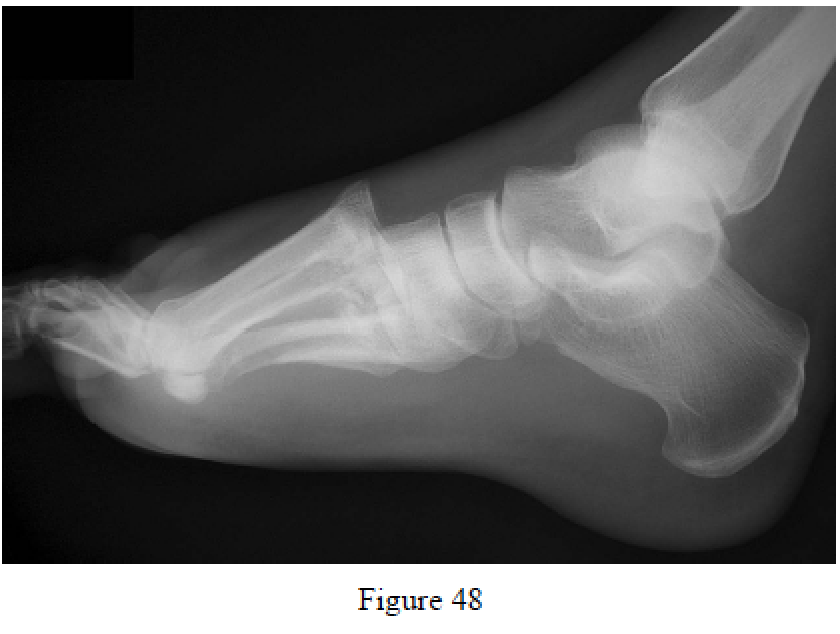

Ly TV, Coetzee JC. Treatment of primarily ligamentous Lisfranc joint injuries: primary arthrodesis compared with open reduction and internal fixation. A prospective, randomized study. J Bone Joint Surg Am. 2006 Mar;88(3):514-20. PubMed PMID: 16510816.